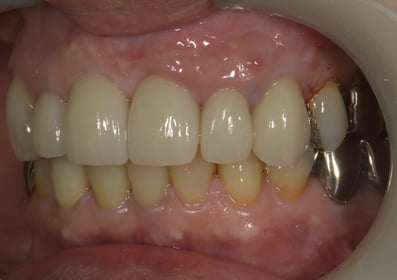

Simplified Microscopic Implant surgical Lifelike Esthetics を略した手術名で、米国カルフォルニア州サンタバーバラで歯周病専門医として開業されていた、 Dr. Dennis Shanelec(故人)が考案した治療法です。抜歯した直後に仮歯を入れることによって,歯を取り巻く骨(硬組織)や歯肉(軟組織)の状態を維持できる非常に優れた方法です。しかし、手術としての難易度は非常に高いレベルに位置づけられます。

抜歯した直後にインプラントを埋入し、仮の歯を作製、唇側の骨のボリュームを保つために人工骨と結合組織を同時に移植する非常に優れた方法です。